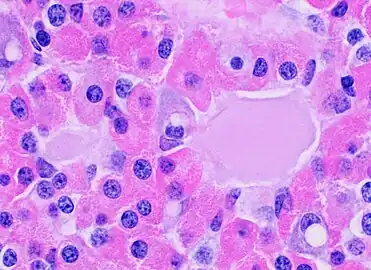

- Pars distalis

The pars distalis (distal part) comprises the majority of the anterior pituitary and is where the bulk of pituitary hormone production occurs. The pars distalis contains two types of cells, including chromophobe cells and chromophil cells.[1] The chromophils can be further divided into acidophils (alpha cells) and basophils (beta cells).[1] These cells all together produce hormones of the anterior pituitary and release them into the blood stream.

Nota bene: The terms "basophil" and "acidophil" are used by some books, whereas others prefer not to use these terms. This is due to the possible confusion with white blood cells, where one may also find basophils and acidophils.

Microanatomy of the pars distalis showing chromophobes, basophils, and acidophils

Microanatomy of the pars distalis showing chromophobes, basophils, and acidophils Eosinophilic follicles are a common normal finding in the anterior pituitary.

Eosinophilic follicles are a common normal finding in the anterior pituitary.